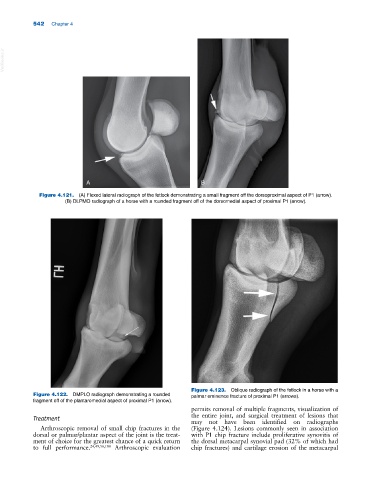

Figure 4.121. (A) Flexed lateral radiograph of the fetlock demonstrating a small fragment off the dorsoproximal aspect of P1 (arrow).

(B) DLPMO radiograph of a horse with a rounded fragment off of the dorsomedial aspect of proximal P1 (arrow).

Figure 4.123. Oblique radiograph of the fetlock in a horse with a

Figure 4.122. DMPLO radiograph demonstrating a rounded palmar eminence fracture of proximal P1 (arrows).

fragment off of the plantaromedial aspect of proximal P1 (arrow).